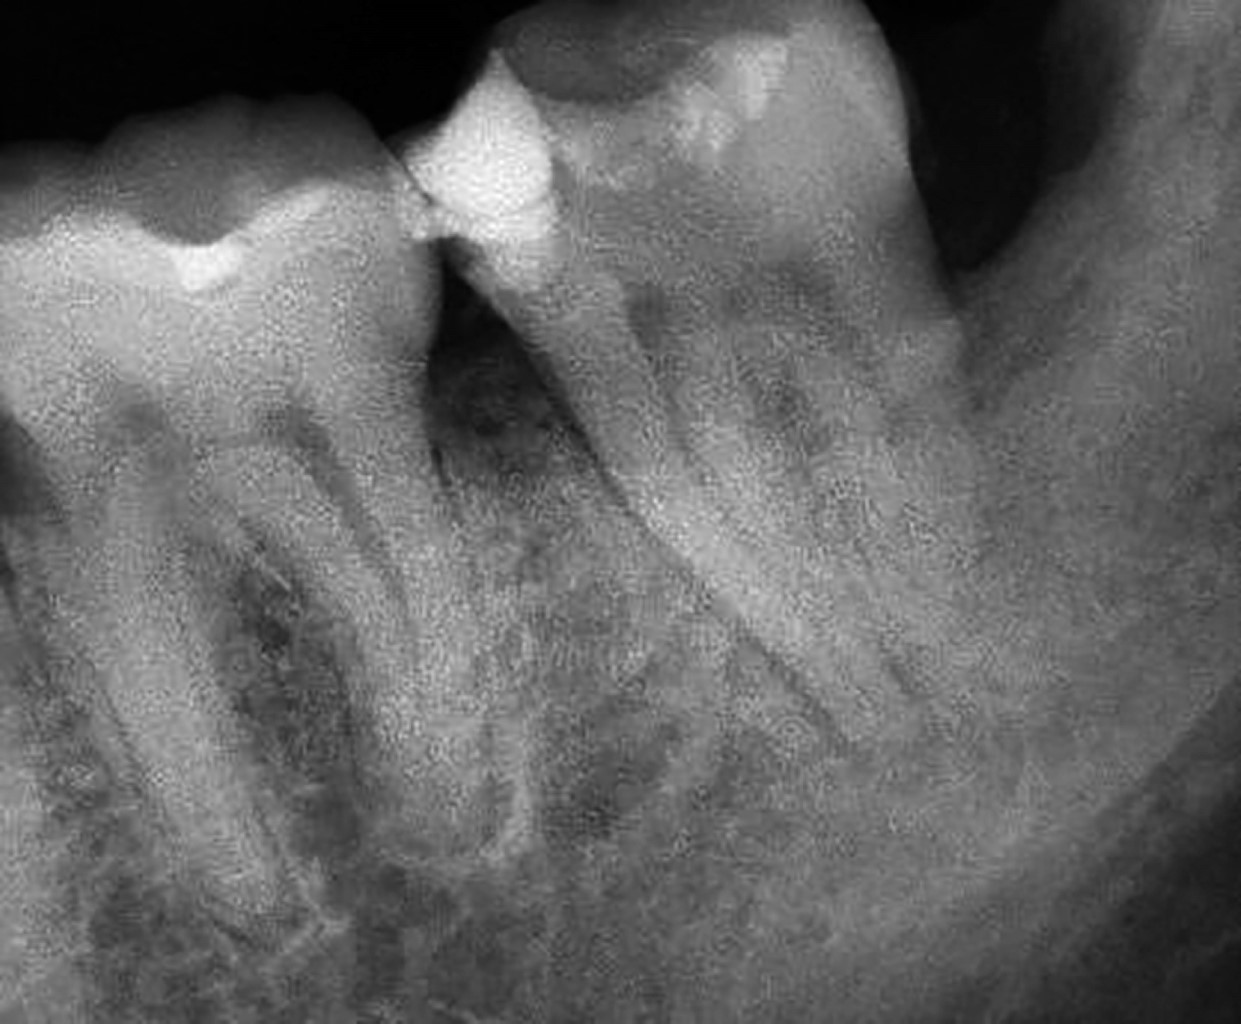

Se decide extraer el tercer molar, procedimiento que fue realizado por un cirujano maxilofacial, sin complicaciones aparentes. Después de tres semanas el paciente acude nuevamente refiriendo dolor en la zona del segundo molar izquierdo, se toma una nueva radiografía donde se observa pérdida de continuidad de la imagen del tercio medio y apical de la raíz distal (Figura 2).

Para finalizar, se colocó resina dual hasta rellenar completamente el acceso endodóncico y el paciente fue regresado con la cirujana dentista que lo refirió, quien le elaboró una restauración coronal completa de metal porcelana. A los seis meses el paciente acude para control radiográfico, refiriendo haber estado asintomático durante este tiempo, podemos observar ausencia de zonas radiolúcidas periapicales, nivel del hueso alveolar satisfactorio, sin aumento del espacio del ligamento periodontal, (Figura 14), por lo que se decide citarlo en un año para nuevo control.

Figura 2

Figura 14